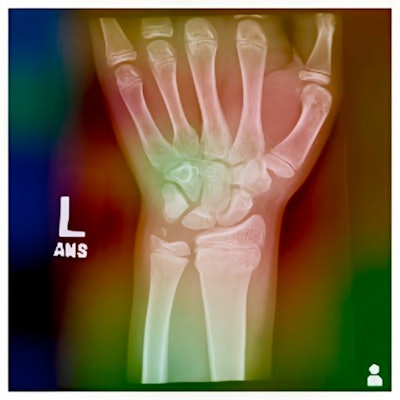

Grad-CAM heatmap of the EfficientNet-B2 model for a sample radiograph.Journal of the Pediatric Orthopaedic Society of North America

In addition, to interpret the model's predictions, the researchers used Grad-CAM, a technique that visualizes the regions of the radiographs that the model learned to focus on for classification.

“Fine-tuning an EfficientNet model can achieve high accuracy in identifying physeal fractures. Further, Grad-CAM provides interpretability and transparency for the model's predictions, highlighting regions of interest and potential sources of error,” the group wrote.